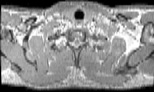

Visible Human male: Sectio transversalis 1292

CT

NMR

Pd T1 T2